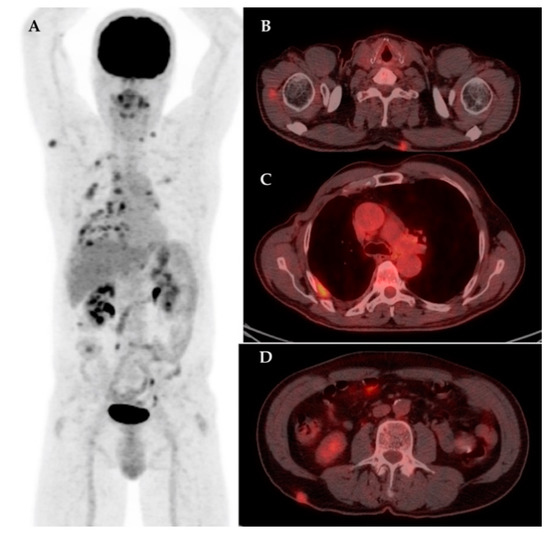

| 7 | 47 | IDC | Biopsy | – | Yes | IIIC | LN | Bn, Sk | 18.36 | – | – |

| 13 | 67 | IDC | RM + ALND | – | – | IIB | LN | LN, L | 4.43 | – | – |

| 19 | 74 | IDC | RM + ALND | Yes | Yes | IIIC | LN, Bn | LN, Sk, M | 6.21 | – | – |